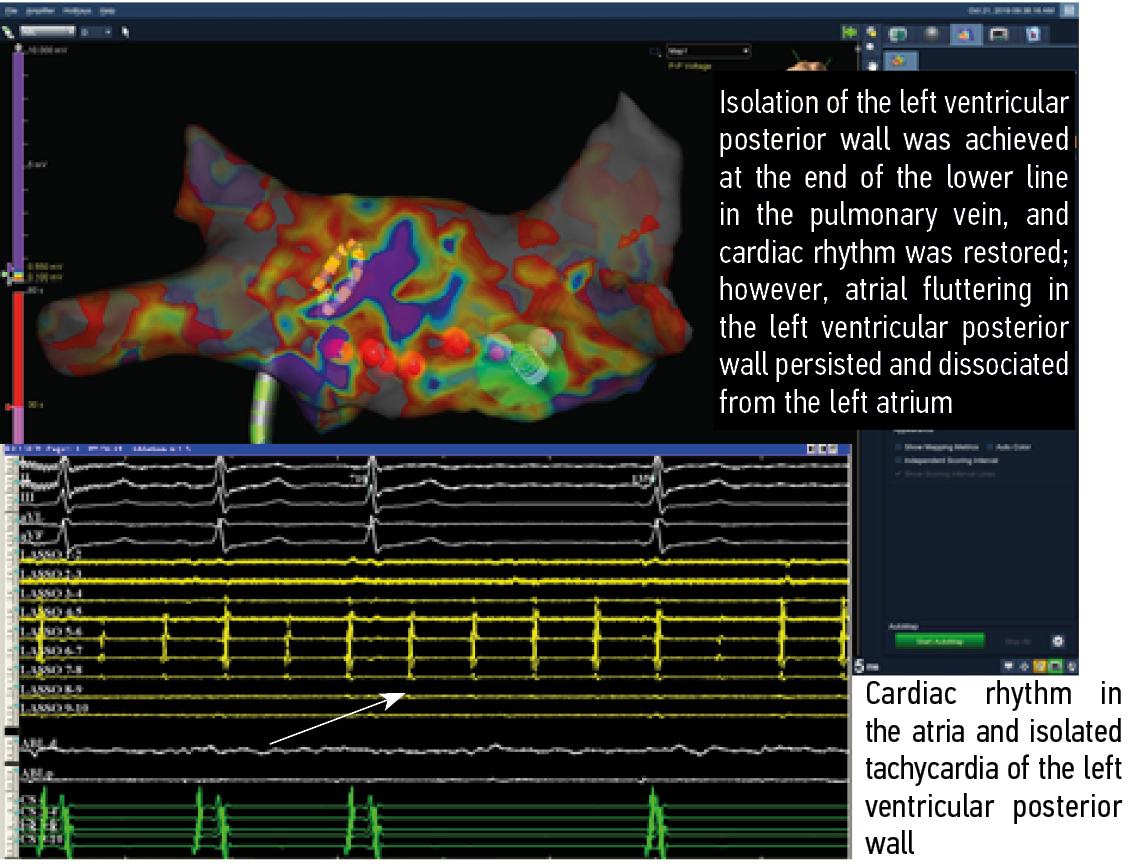

Fig. 4. Relief of tachycardia in the posterior anastomosis on the right. Top–down: amplitude map of the patient, standard leads of the electrocardiogram, and signals from the multipole circular electrode (yellow) on the posterior wall of the left atrium. The arrows indicate the absence of activity from the anastomosis on the right, where the treatment electrode is located. White, signals from the ablation electrode; green, signals from the multipole electrode in the coronary sinus. The Claris EPT system (Abbott, USA) was used. The recording speed was 200 mm/s

Рис. 4. Купирование тахикардии в заднем соустье справа. Сверху вниз: амплитудная карта пациента, стандартные отведения электрокардиограммы, сигналы с многополюсного циркулярного электрода (желтые) на задней стенке левого предсердия стрелками указано отсутствие активности с соустья справа, там, где располагается лечебный электрод, сигналы с аблационного электрода (белые), сигналы с многополюсного электрода в коронарном синусе (зеленые). ЭФИ-система Claris (Abbot, США). Скорость записи 200 мм/с